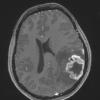

NEOPLASMS (GLIAL)

Pleomorphic Xanthoastrocytoma (PXA) (14)